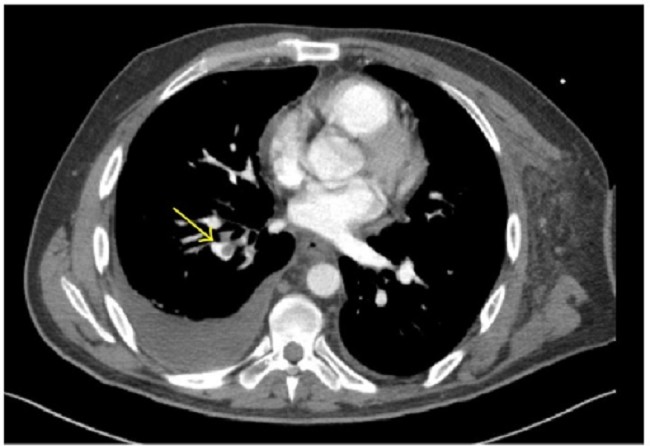

Gambar 1. CT angiografi emboli paru. (Sumber : Openi, 2014)

Tes laboratorium seperti kadar D-dimer, dikombinasikan menggunakan sistem skor Kriteria Well’s, dapat membantu penilaian risiko, tetapi hasil positif sebaiknya dikonfirmasi melalui modalitas pencitraan seperti computed tomography pulmonary angiography (CTPA) atau pemindaian ventilasi-perfusi (V/Q). Teknik pencitraan ini mampu memvisualisasikan pembuluh darah paru dan pola perfusi.